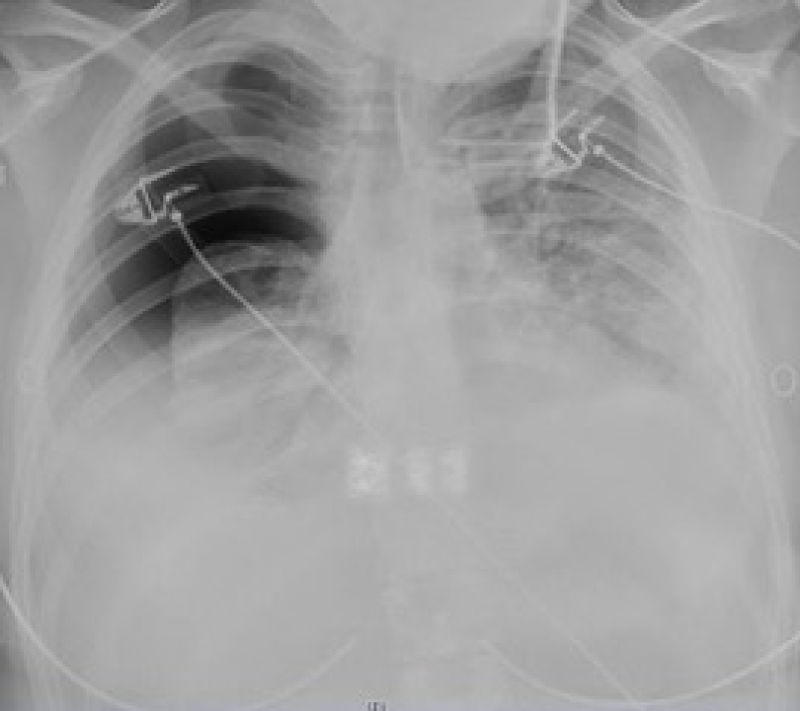

A further CT scan was performed which demonstrated a right submandibular & hypopharyngeal fluid collection with peritonsillar inflammation in the presence of right subclavian and jugular vein thrombosis. It was felt that these features were indicative of Lemierre's Syndrome (LS). The bilateral pleural collections had progressed significantly, to the extent that virtually no aerated lung was present on either side. The diagnosis of LS was confirmed when pleural fluid samples were found to contain Prevotella veroralis and Fusobacterium necrophorum (Figure 3).

Figure 3: Computed tomography demonstrating the absence of aerated lung. View Figure 3